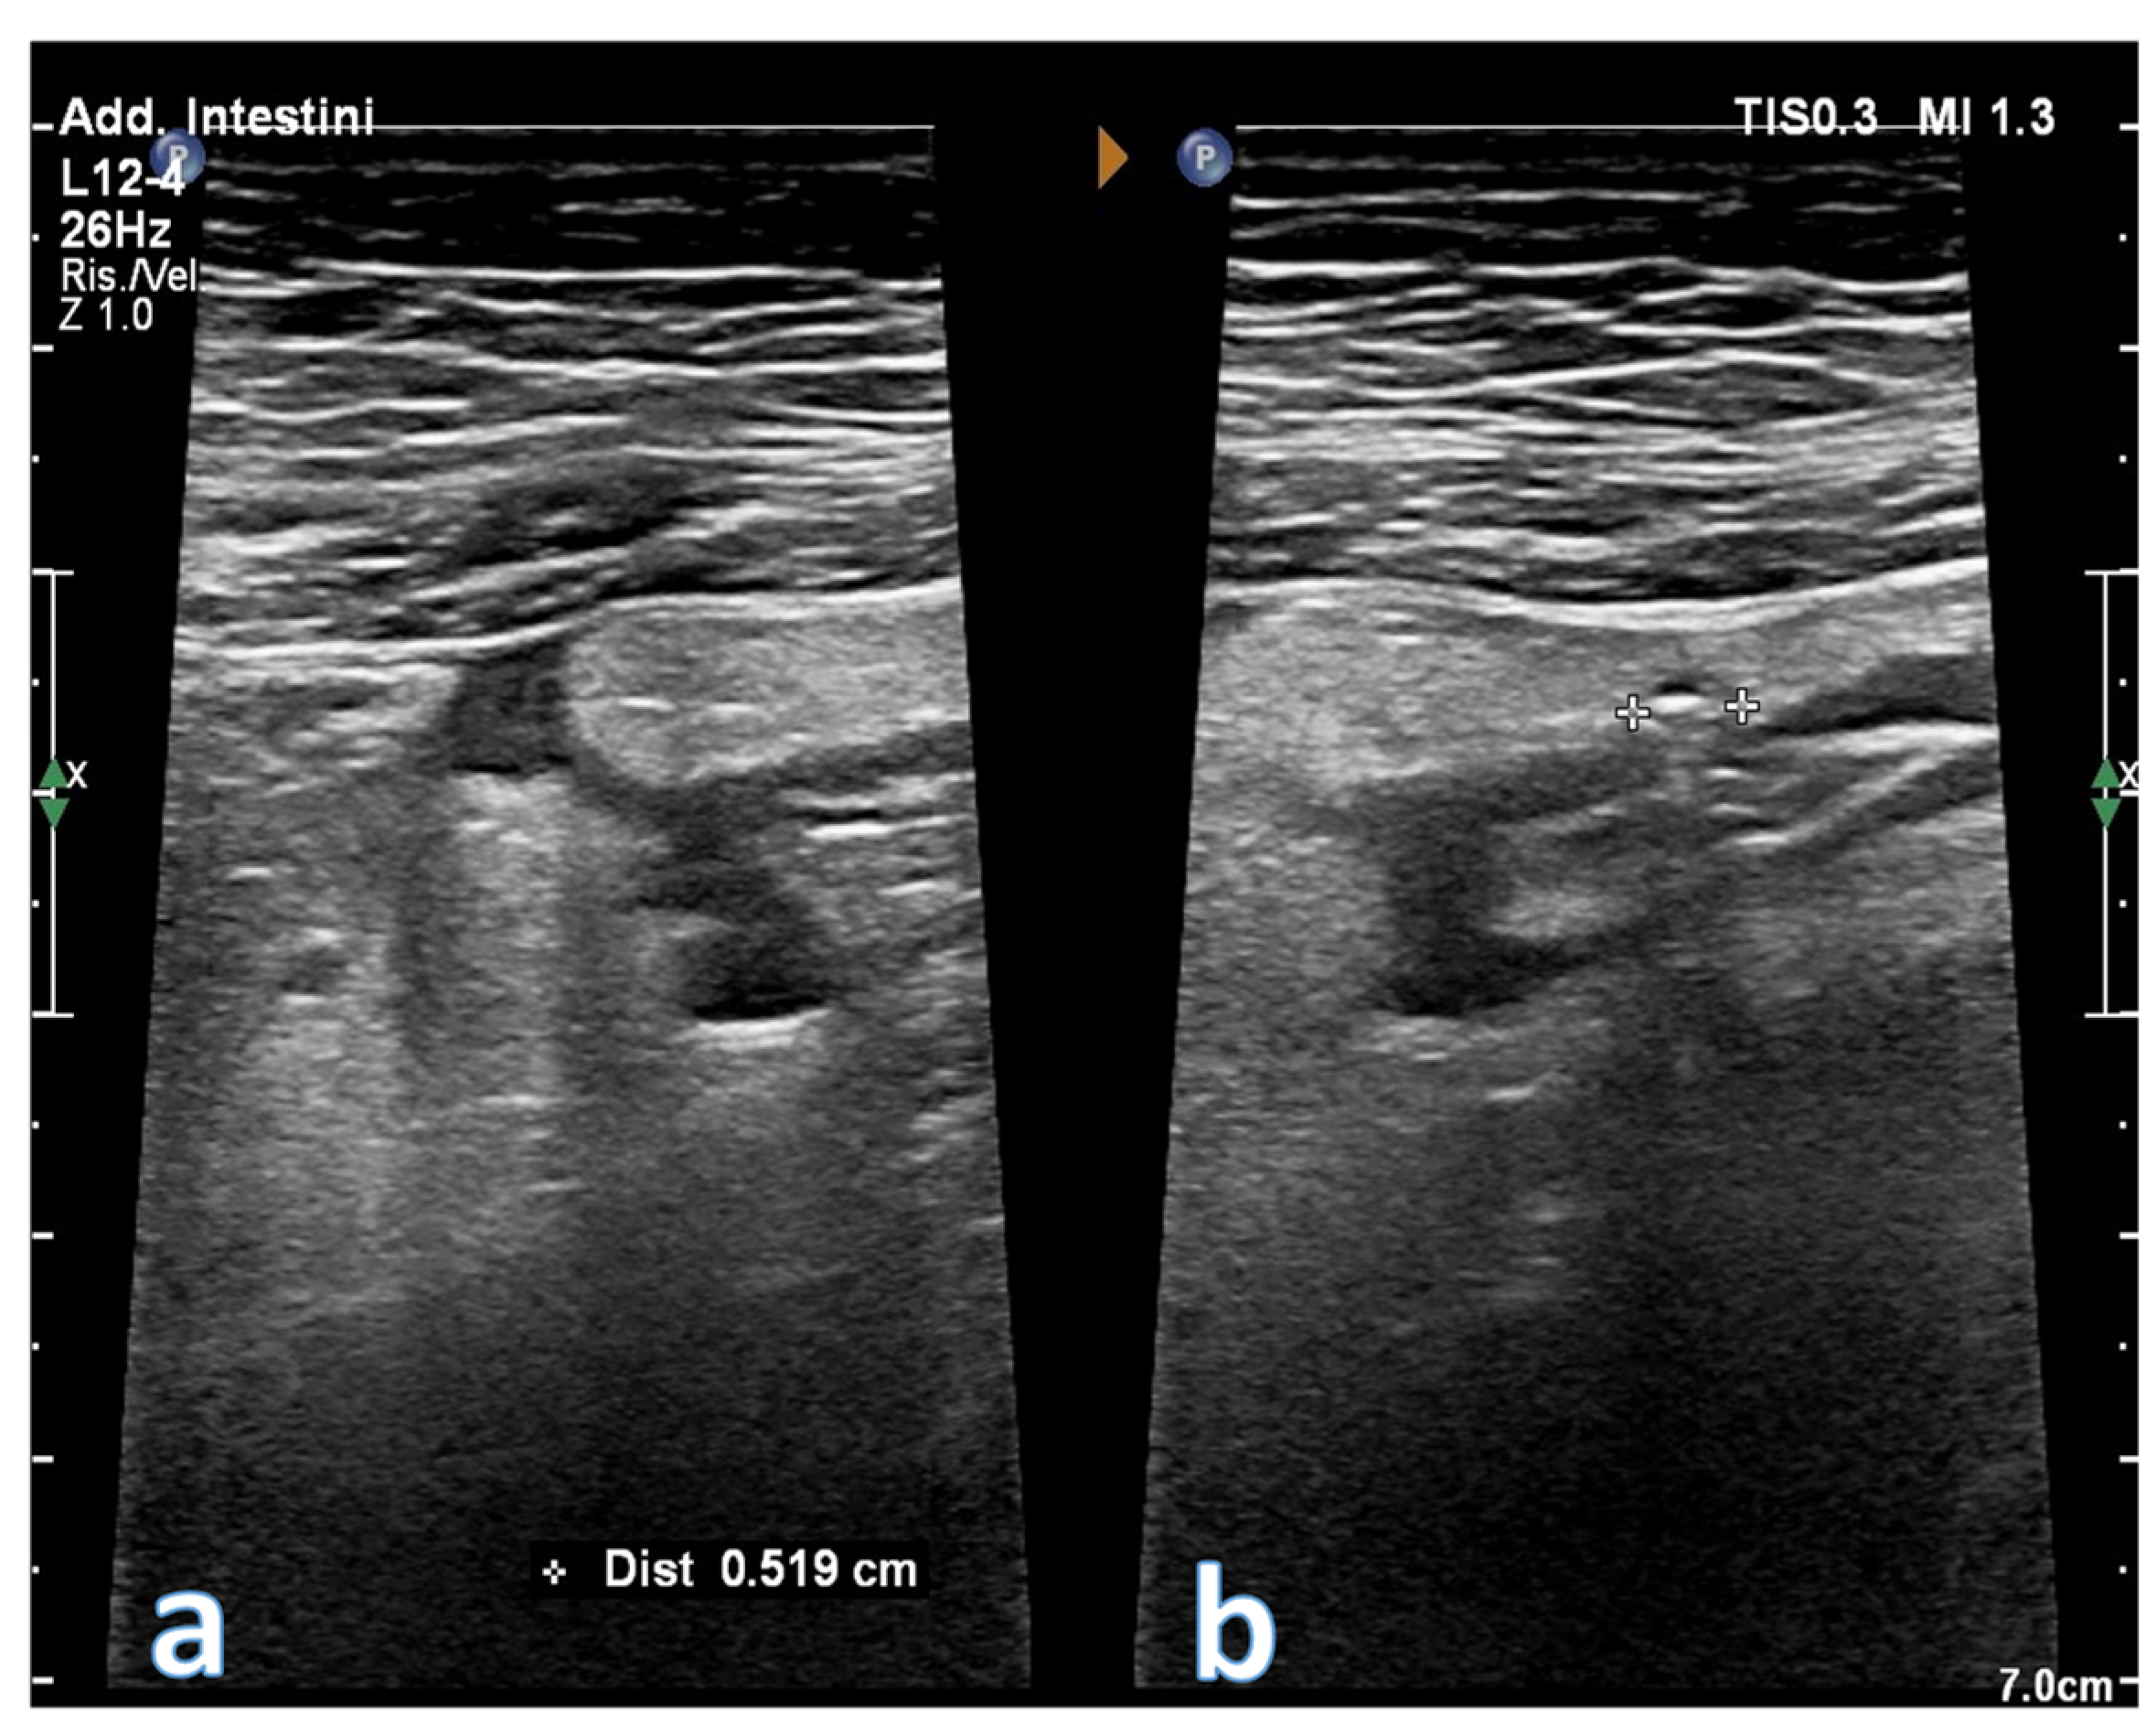

5. Acute Diverticulitis

- Valentino, M.; Serra, C.; Ansaloni, L.; Mantovani, G.; Pavlica, P.; Barozzi, L. Sonographic features of acute colonic diverticulitis. J. Clin. Ultrasound. 2009, 37, 457–463. [Google Scholar] [CrossRef] [PubMed]